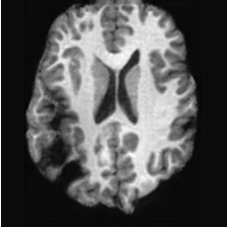

PathologicalHealthyDifferencew/o ACGw/ ACG(a)Refer to captionRefer to captionRefer to captionRefer to captionRefer to captionHealthyPathologicalDifferencew/o ACGw/ ACG(b)Refer to captionRefer to captionRefer to captionRefer to captionRefer to caption

Figure 6: Ablation study of Anatomy Consistency Guidance (ACG): (a) pathology-to-healthy; (b) healthy-to-pathology. Without ACG, edits cause anatomical inconsistencies outside lesions (arrows), whereas ACG keeps modifications lesion-focused.

Anomaly Consistency Guidance. Fig. 6 demonstrates the effectiveness of the proposed Anatomy Consistency Guidance (ACG) on bidirectional editing. Without ACG, the generated brains exhibit noticeable and unrealistic anatomical deformations in non-lesion regions (arrow-indicated), leading to structural inconsistencies between the edited and original brains, as shown in the corresponding difference maps. After incorporating ACG, the model effectively constrains editable modifications within pathological regions, while preserving the remaining anatomy. Tab. 4 further reports their quantitative performances: removing ACG leads to a substantial degradation in all L1, PSNR, and SSIM scores, reaffirming the critical role of ACG in achieving more accurate and structurally consistent reconstructions.